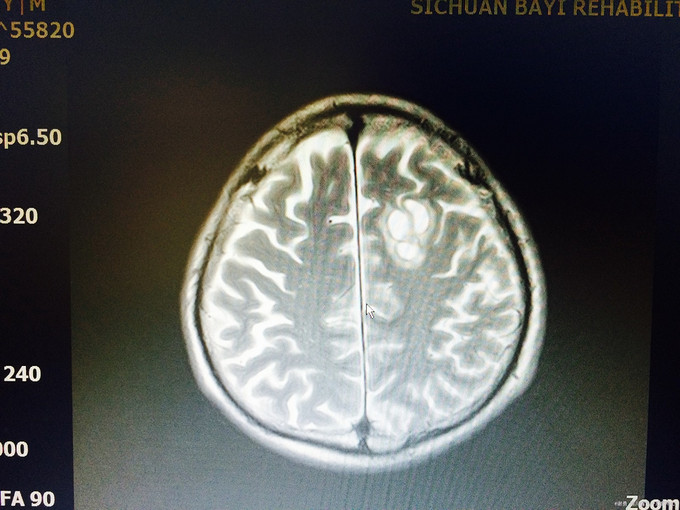

入院查体:生命体征平稳,高级皮层功能正常;四肢肌张力不高,肌力5级,病理征未引出;头颅MRI示:左侧额叶皮层下见23*15*16mm“多囊状”异常信号,见等信号囊壁,周边少许水肿信号,增强信号见病灶壁环形强化,边缘一结节状强化,肿瘤?脑囊虫病?左颞叶、顶叶、颞叶多个结节状,长T1长T2信号,FLAIR呈高信号;左颞叶见一强化“小结节”; 入院诊断:颅内占位改变,性质待定:脑膜瘤?脑囊虫病?